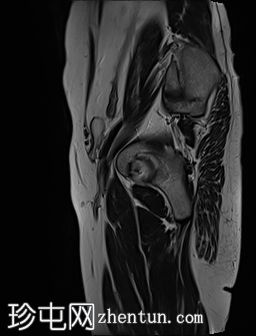

MRI

左侧阴囊空虚。

左侧睾丸位于盆腔左侧前壁,腹股沟管上方。其体积较小(与对侧正常的右侧睾丸相比)。T2加权像呈高信号,T1加权像呈低信号,未见明显局灶

性病

变。

右侧睾丸位于右侧阴囊内,大小和形状正常。